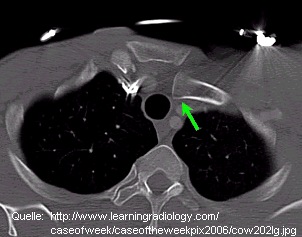

Ursachen für die Sternoclavicular-Luxation sind heutzutage meist Verkehrsunfälle (ca. 50%), Sportverletzungen (ca. 25%, häufig Kampfsportarten) und Stürze auf die Schulter (ca. 20%). Im Alten Ägypten dürften Kriegsverwundungen und Arbeitsunfälle führend gewesen sein. Es handelt sich in der Regel um indirekte Gewalteinwirkungen durch einen sehr harten Schlag gegen oder Sturz auf die Schulter, welche dabei zusätzlich nach ventral oder dorsal verdreht wird. Hierdurch erhöht sich der Stress auf das Sternoclavicular-Gelenk derart, daß es zur Luxation (durch den Zug des M. sternocleidomastoideus meist nach vorn oben = Luxatio sternoclavicularis anterior) kommt. Durch direkte Gewalteinwirkung auf das Gelenk kann der Schlüsselbeinkopf auch hinter das Brustbein verlagert werden (Luxatio sternoclavicularis posterior). Diese kann zu lebensbedrohlichen Verletzungen von Lunge, Herz, Luft-/Speiseröhre und großen Gefäßen führen.

Diagnostik: Der Verletzte weiß bei einer anterioren Luxation meist sofort, daß sein Gelenk ”ausgekugelt” ist. Untrügbare Anzeichen hierfür sind nach einem typischen Unfallmechanismus insbesondere der plötzliche, überaus heftige Schmerz im Gelenkbereich, die sichtbare und tastbare Dislokation des Schlüsselbeinkopfes nach vorn oben (Abb. links) sowie die Bewegungseinschränkung im Schultergürtel. Bei einer posterioren Luxation muß die Verschiebung allerdings nicht sicht- oder tastbar sein; hier bringt meist erst eine Röntgen- oder CT-Untersuchung (Abb. rechts) Sicherheit.